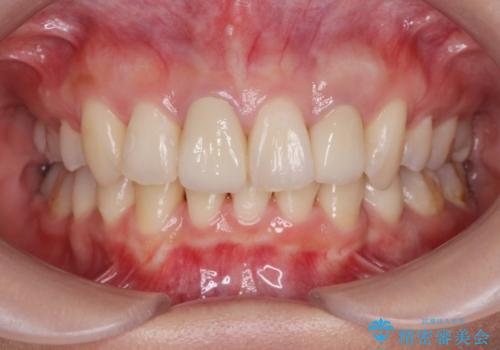

[マルチブラケットで後方移動] ワイヤー矯正で行う噛み合わせの改善